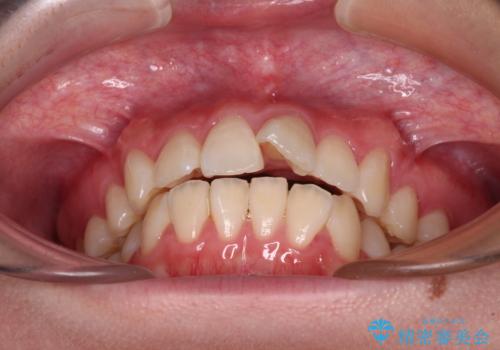

- 前歯がくちばしのように飛び出していることを気にして来院された患者様です。

唇が前方に突出している横顔が気になっているため、上下左右の第一小臼歯4本を抜歯し、ワイヤー装置にて矯正治療を行うこととしました。